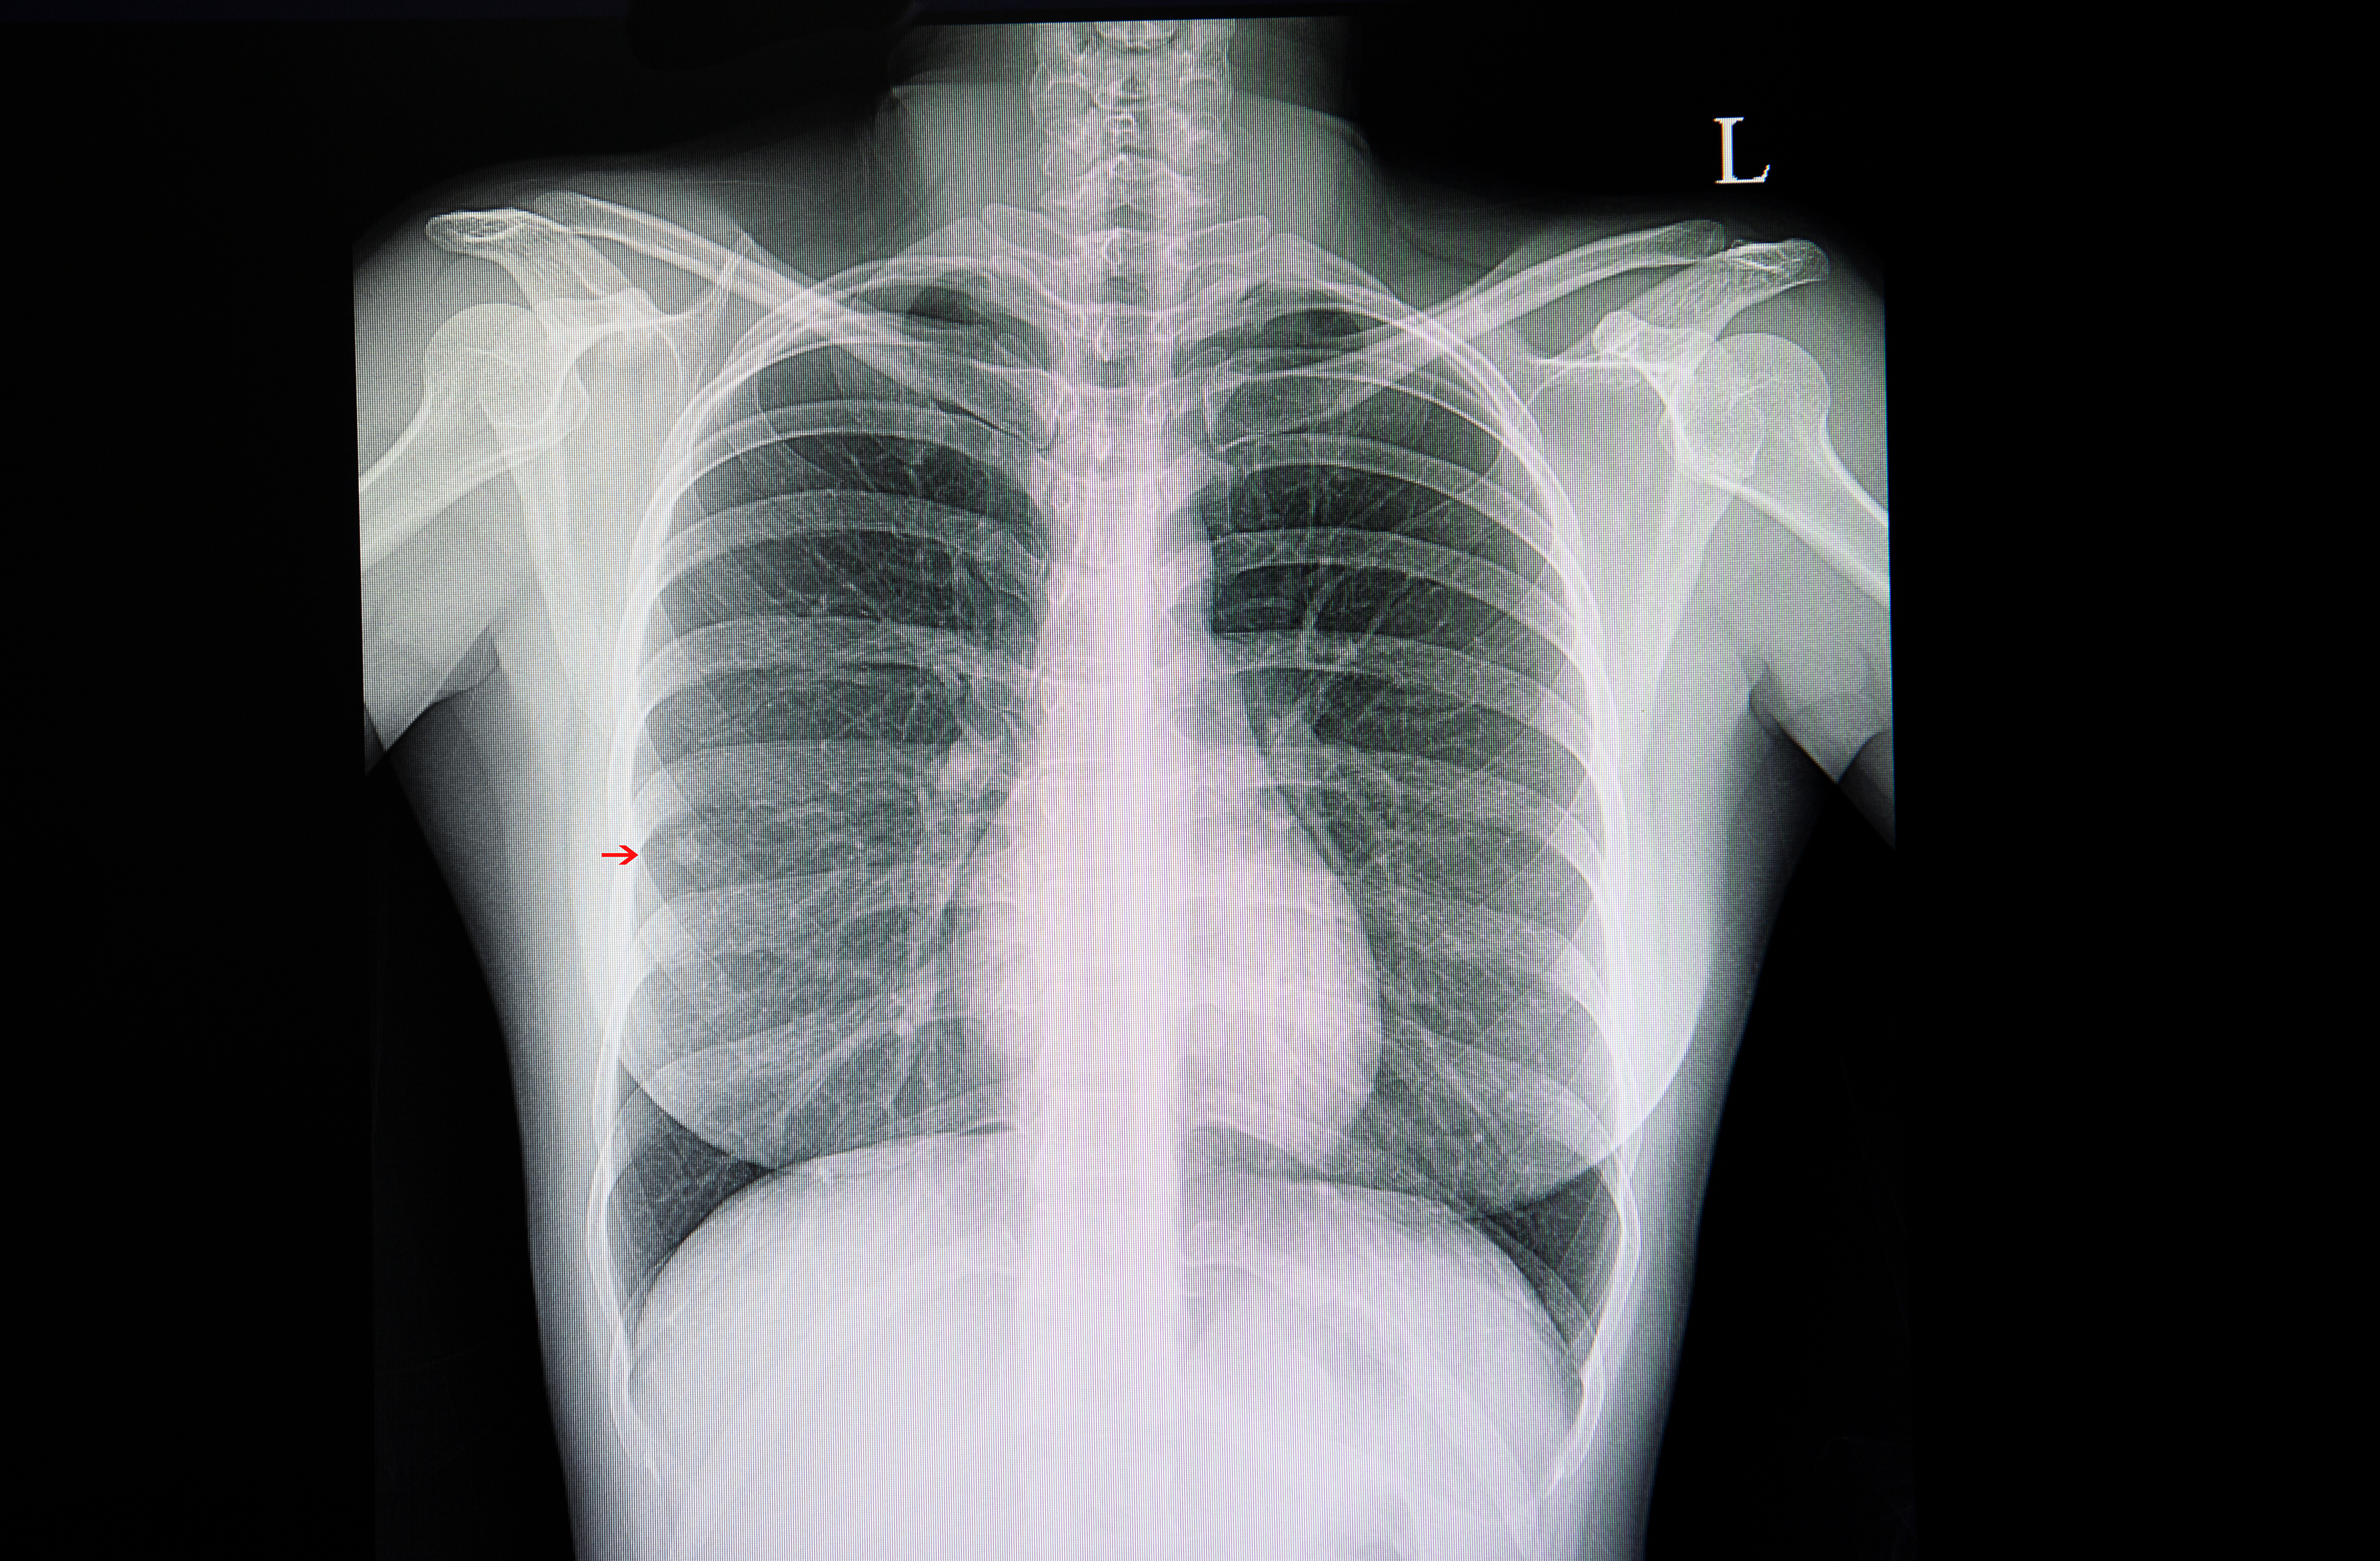

In an external validation data set for a deep learning bone-suppressed (DLBS) model, researchers found that adjunctive use of the DLBS model led to a nearly 15 percent increase in sensitivity for detecting pulmonary nodules on chest X-rays in comparison to radiologist assessment.